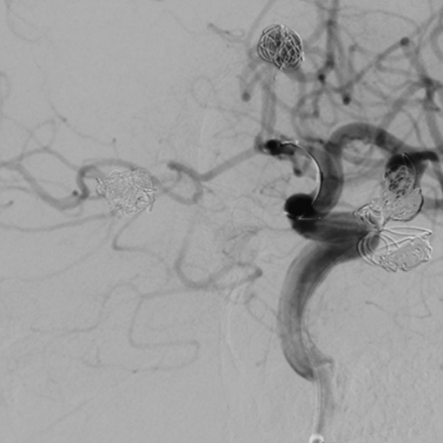

Post-treatment imaging of the left middle cerebral recurrent aneurysm and left anterior cerebral saccular aneurysm

Working position angiography of the right internal carotid artery

Surgical Procedure

After successfully treating the left-sided aneurysms, the team proceeded to use the Nuva® Flow Diverter for the right posterior communicating artery aneurysm. The decision was made based on several advantages of the Nuva® system, including its radiopaque release-recapture segment that provides navigational guidance, full stent visibility for real-time wall apposition assessment, and the super-elastic nitinol braided structure that enhances flexibility and conformability.

According to the lesion measurements, the team selected the Nuva® Flow Diverter TJED-D-5.0-20 (designed for vessels approximately 4.5 mm in diameter and 28 mm in length).